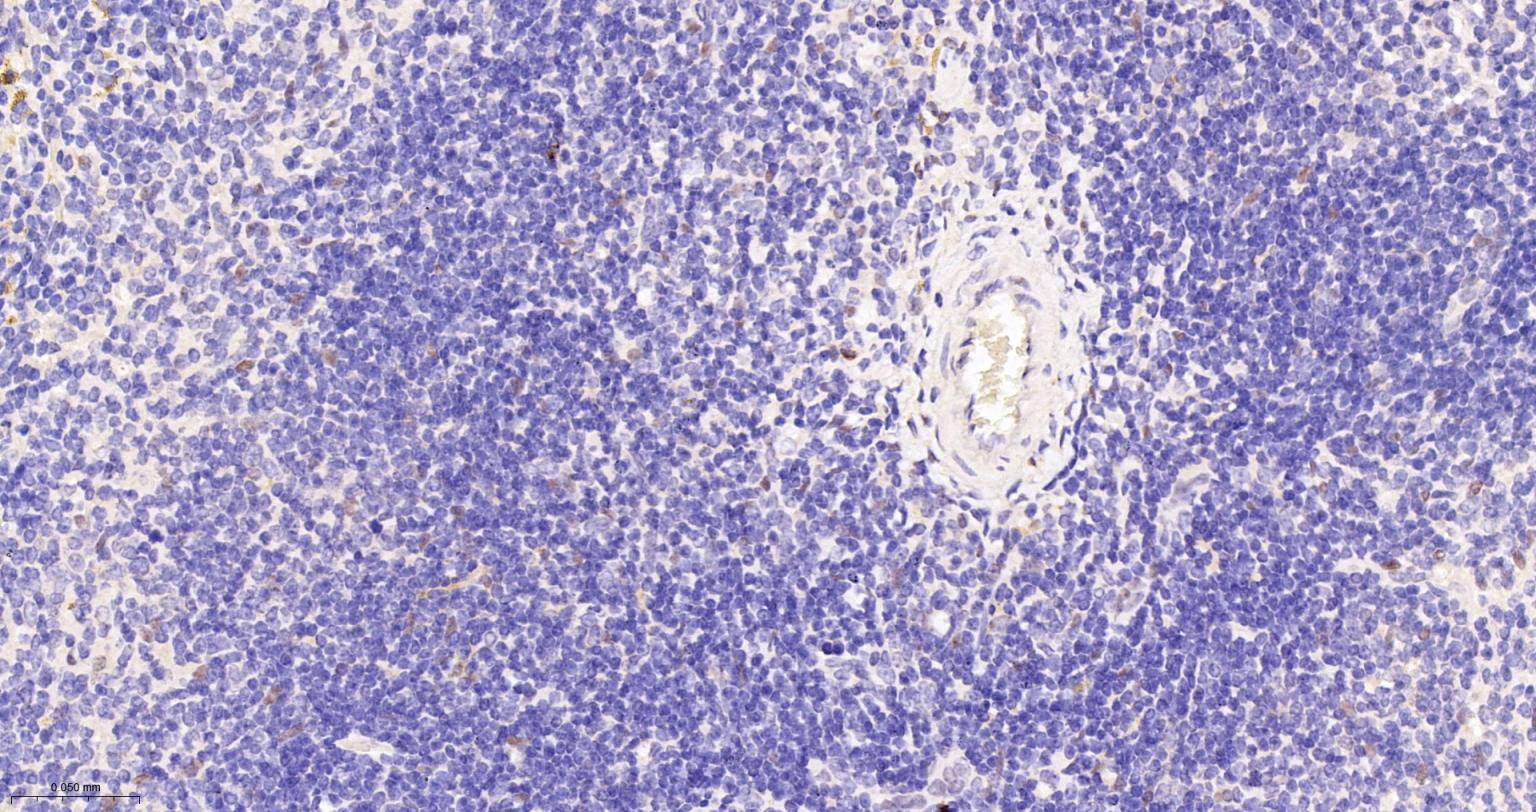

Paraformaldehyde-fixed, paraffin embedded Human Spleen; Antigen retrieval by boiling in sodium citrate buffer (pH6.0) for 15 min; The section was incubated with TEAD1 Monoclonal Antibody, Unconjugated (bsm-63274R) at 1:200 overnight at 4°C, followed by conjugation to the bs-0295G-HRP and DAB (C-0010) staining.